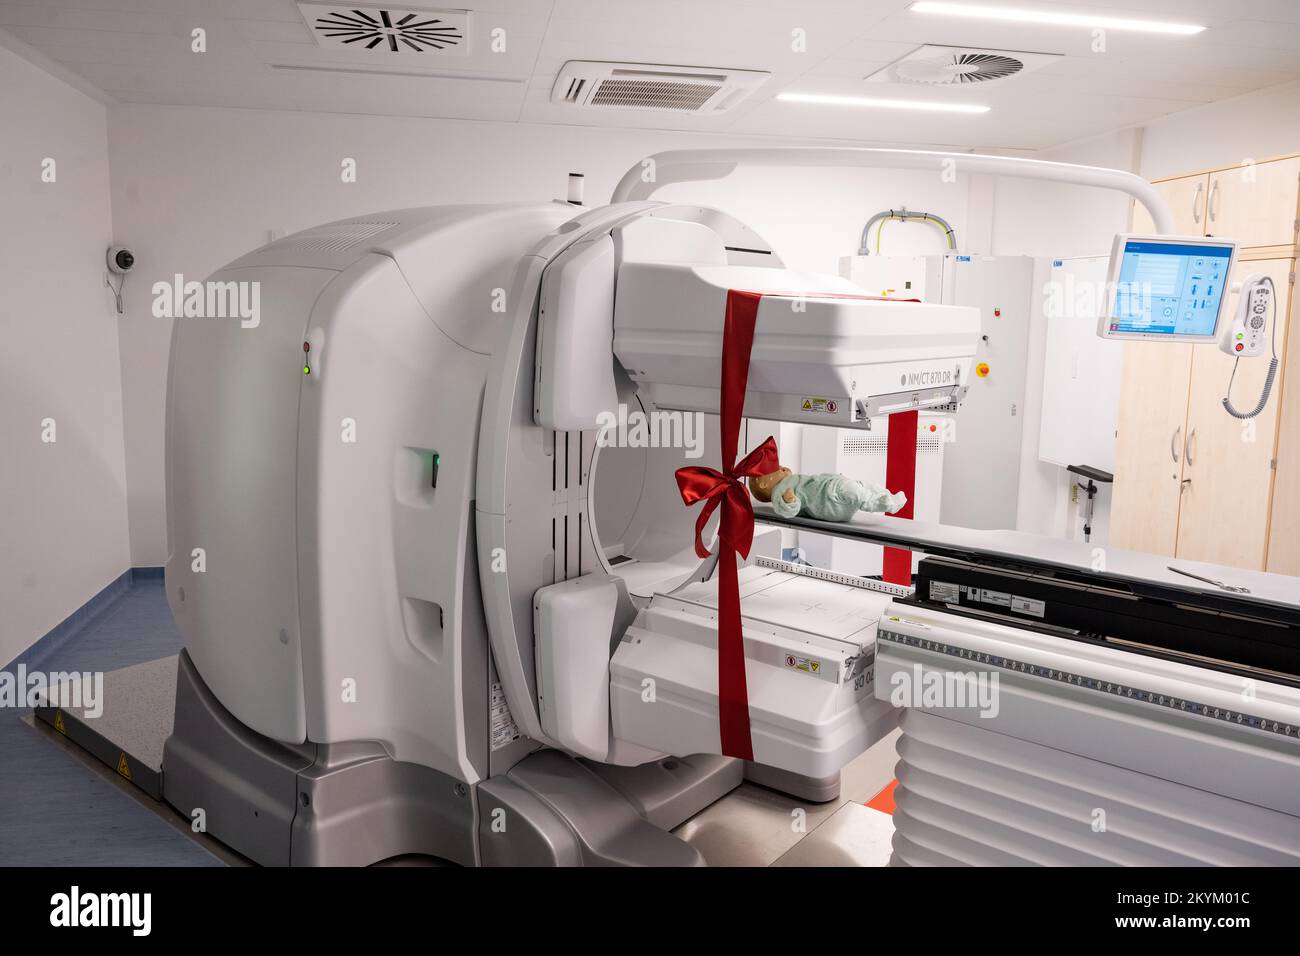

RM2KYKWRY–01 décembre 2022, Mecklembourg-Poméranie occidentale, Greifswald: Une unité NM/CT 870 DR de General Electric Medical Systems, Israël est sur le point d'être remise dans les salles de la clinique pédiatrique du centre médical de l'université Greifswald. Ce système SPECT/CT permet des examens médicaux nucléaires encore plus précis. Ceci est nécessaire pour les options de traitement spéciales telles que la thérapie par radio-isotope. La tomodensitométrie (CT) utilise un grand nombre d'images radiologiques pour calculer les images numériques. Une acquisition SPECT, en revanche, utilise une caméra gamma pour rendre visible le faible rayonnement des médicaments radioactifs. Dans cette wa

RM2KYKWRC–01 décembre 2022, Mecklembourg-Poméranie occidentale, Greifswald: Une unité NM/CT 870 DR de General Electric Medical Systems, Israël est sur le point d'être remise dans les salles de la clinique pédiatrique du centre médical de l'université Greifswald. Ce système SPECT/CT permet des examens médicaux nucléaires encore plus précis. Ceci est nécessaire pour les options de traitement spéciales telles que la thérapie par radio-isotope. La tomodensitométrie (CT) utilise un grand nombre d'images radiologiques pour calculer les images numériques. Une acquisition SPECT, en revanche, utilise une caméra gamma pour rendre visible le faible rayonnement des médicaments radioactifs. Dans cette wa

RM2KYM017–01 décembre 2022, Mecklembourg-Poméranie occidentale, Greifswald: Un dispositif NM/CT 870 DR de General Electric Medical Systems, Israël est sur le point d'être remis dans les salles de la clinique pédiatrique du centre médical de l'université de Greifswald. Ce système SPECT/CT permet des examens médicaux nucléaires encore plus précis. Ceci est nécessaire pour les options de traitement spéciales telles que la thérapie par radio-isotope. La tomodensitométrie (CT) utilise un grand nombre d'images radiologiques pour calculer les images numériques. Une acquisition SPECT, en revanche, utilise une caméra gamma pour rendre visible le faible rayonnement des médicaments radioactifs. Dans cette

RM2KYM01N–01 décembre 2022, Mecklembourg-Poméranie occidentale, Greifswald: Une unité NM/CT 870 DR de General Electric Medical Systems, Israël est sur le point d'être remise dans les salles de la clinique pédiatrique du centre médical de l'université Greifswald. Ce système SPECT/CT permet des examens médicaux nucléaires encore plus précis. Ceci est nécessaire pour les options de traitement spéciales telles que la thérapie par radio-isotope. La tomodensitométrie (CT) utilise un grand nombre d'images radiologiques pour calculer les images numériques. Une acquisition SPECT, en revanche, utilise une caméra gamma pour rendre visible le faible rayonnement des médicaments radioactifs. Dans cette wa

RM2KYKWW0–01 décembre 2022, Mecklembourg-Poméranie occidentale, Greifswald: Une unité NM/CT 870 DR de General Electric Medical Systems, Israël est sur le point d'être remise dans les salles de la clinique pédiatrique du centre médical de l'université Greifswald. Ce système SPECT/CT permet des examens médicaux nucléaires encore plus précis. Ceci est nécessaire pour les options de traitement spéciales telles que la thérapie par radio-isotope. La tomodensitométrie (CT) utilise un grand nombre d'images radiologiques pour calculer les images numériques. Une acquisition SPECT, en revanche, utilise une caméra gamma pour rendre visible le faible rayonnement des médicaments radioactifs. Dans cette wa

RM2KYKWT3–01 décembre 2022, Mecklembourg-Poméranie occidentale, Greifswald: Une unité NM/CT 870 DR de General Electric Medical Systems, Israël est sur le point d'être remise dans les salles de la clinique pédiatrique du centre médical de l'université Greifswald. Ce système SPECT/CT permet des examens médicaux nucléaires encore plus précis. Ceci est nécessaire pour les options de traitement spéciales telles que la thérapie par radio-isotope. La tomodensitométrie (CT) utilise un grand nombre d'images radiologiques pour calculer les images numériques. Une acquisition SPECT, en revanche, utilise une caméra gamma pour rendre visible le faible rayonnement des médicaments radioactifs. Dans cette wa

RM2KYM01B–01 décembre 2022, Mecklembourg-Poméranie occidentale, Greifswald: Un dispositif NM/CT 870 DR de General Electric Medical Systems, Israël est sur le point d'être remis dans les salles de la clinique pédiatrique du centre médical de l'université de Greifswald. Ce système SPECT/CT permet des examens médicaux nucléaires encore plus précis. Ceci est nécessaire pour les options de traitement spéciales telles que la thérapie par radio-isotope. La tomodensitométrie (CT) utilise un grand nombre d'images radiologiques pour calculer les images numériques. Une acquisition SPECT, en revanche, utilise une caméra gamma pour rendre visible le faible rayonnement des médicaments radioactifs. Dans cette

RM2KYM01C–01 décembre 2022, Mecklembourg-Poméranie occidentale, Greifswald: Une unité NM/CT 870 DR de General Electric Medical Systems, Israël est sur le point d'être remise dans les salles de la clinique pédiatrique du centre médical de l'université Greifswald. Ce système SPECT/CT permet des examens médicaux nucléaires encore plus précis. Ceci est nécessaire pour les options de traitement spéciales telles que la thérapie par radio-isotope. La tomodensitométrie (CT) utilise un grand nombre d'images radiologiques pour calculer les images numériques. Une acquisition SPECT, en revanche, utilise une caméra gamma pour rendre visible le faible rayonnement des médicaments radioactifs. Dans cette wa

RM2KYKWRP–01 décembre 2022, Mecklembourg-Poméranie occidentale, Greifswald: Un dispositif NM/CT 870 DR de General Electric Medical Systems, Israël est sur le point d'être remis dans les salles de la clinique pédiatrique du centre médical de l'université de Greifswald. Ce système SPECT/CT permet des examens médicaux nucléaires encore plus précis. Ceci est nécessaire pour les options de traitement spéciales telles que la thérapie par radio-isotope. La tomodensitométrie (CT) utilise un grand nombre d'images radiologiques pour calculer les images numériques. Une acquisition SPECT, en revanche, utilise une caméra gamma pour rendre visible le faible rayonnement des médicaments radioactifs. Dans cette

RM2KYM01E–01 décembre 2022, Mecklembourg-Poméranie occidentale, Greifswald: Une unité NM/CT 870 DR de General Electric Medical Systems, Israël est sur le point d'être remise dans les salles de la clinique pédiatrique du centre médical de l'université Greifswald. Ce système SPECT/CT permet des examens médicaux nucléaires encore plus précis. Ceci est nécessaire pour les options de traitement spéciales telles que la thérapie par radio-isotope. La tomodensitométrie (CT) utilise un grand nombre d'images radiologiques pour calculer les images numériques. Une acquisition SPECT, en revanche, utilise une caméra gamma pour rendre visible le faible rayonnement des médicaments radioactifs. Dans cette wa